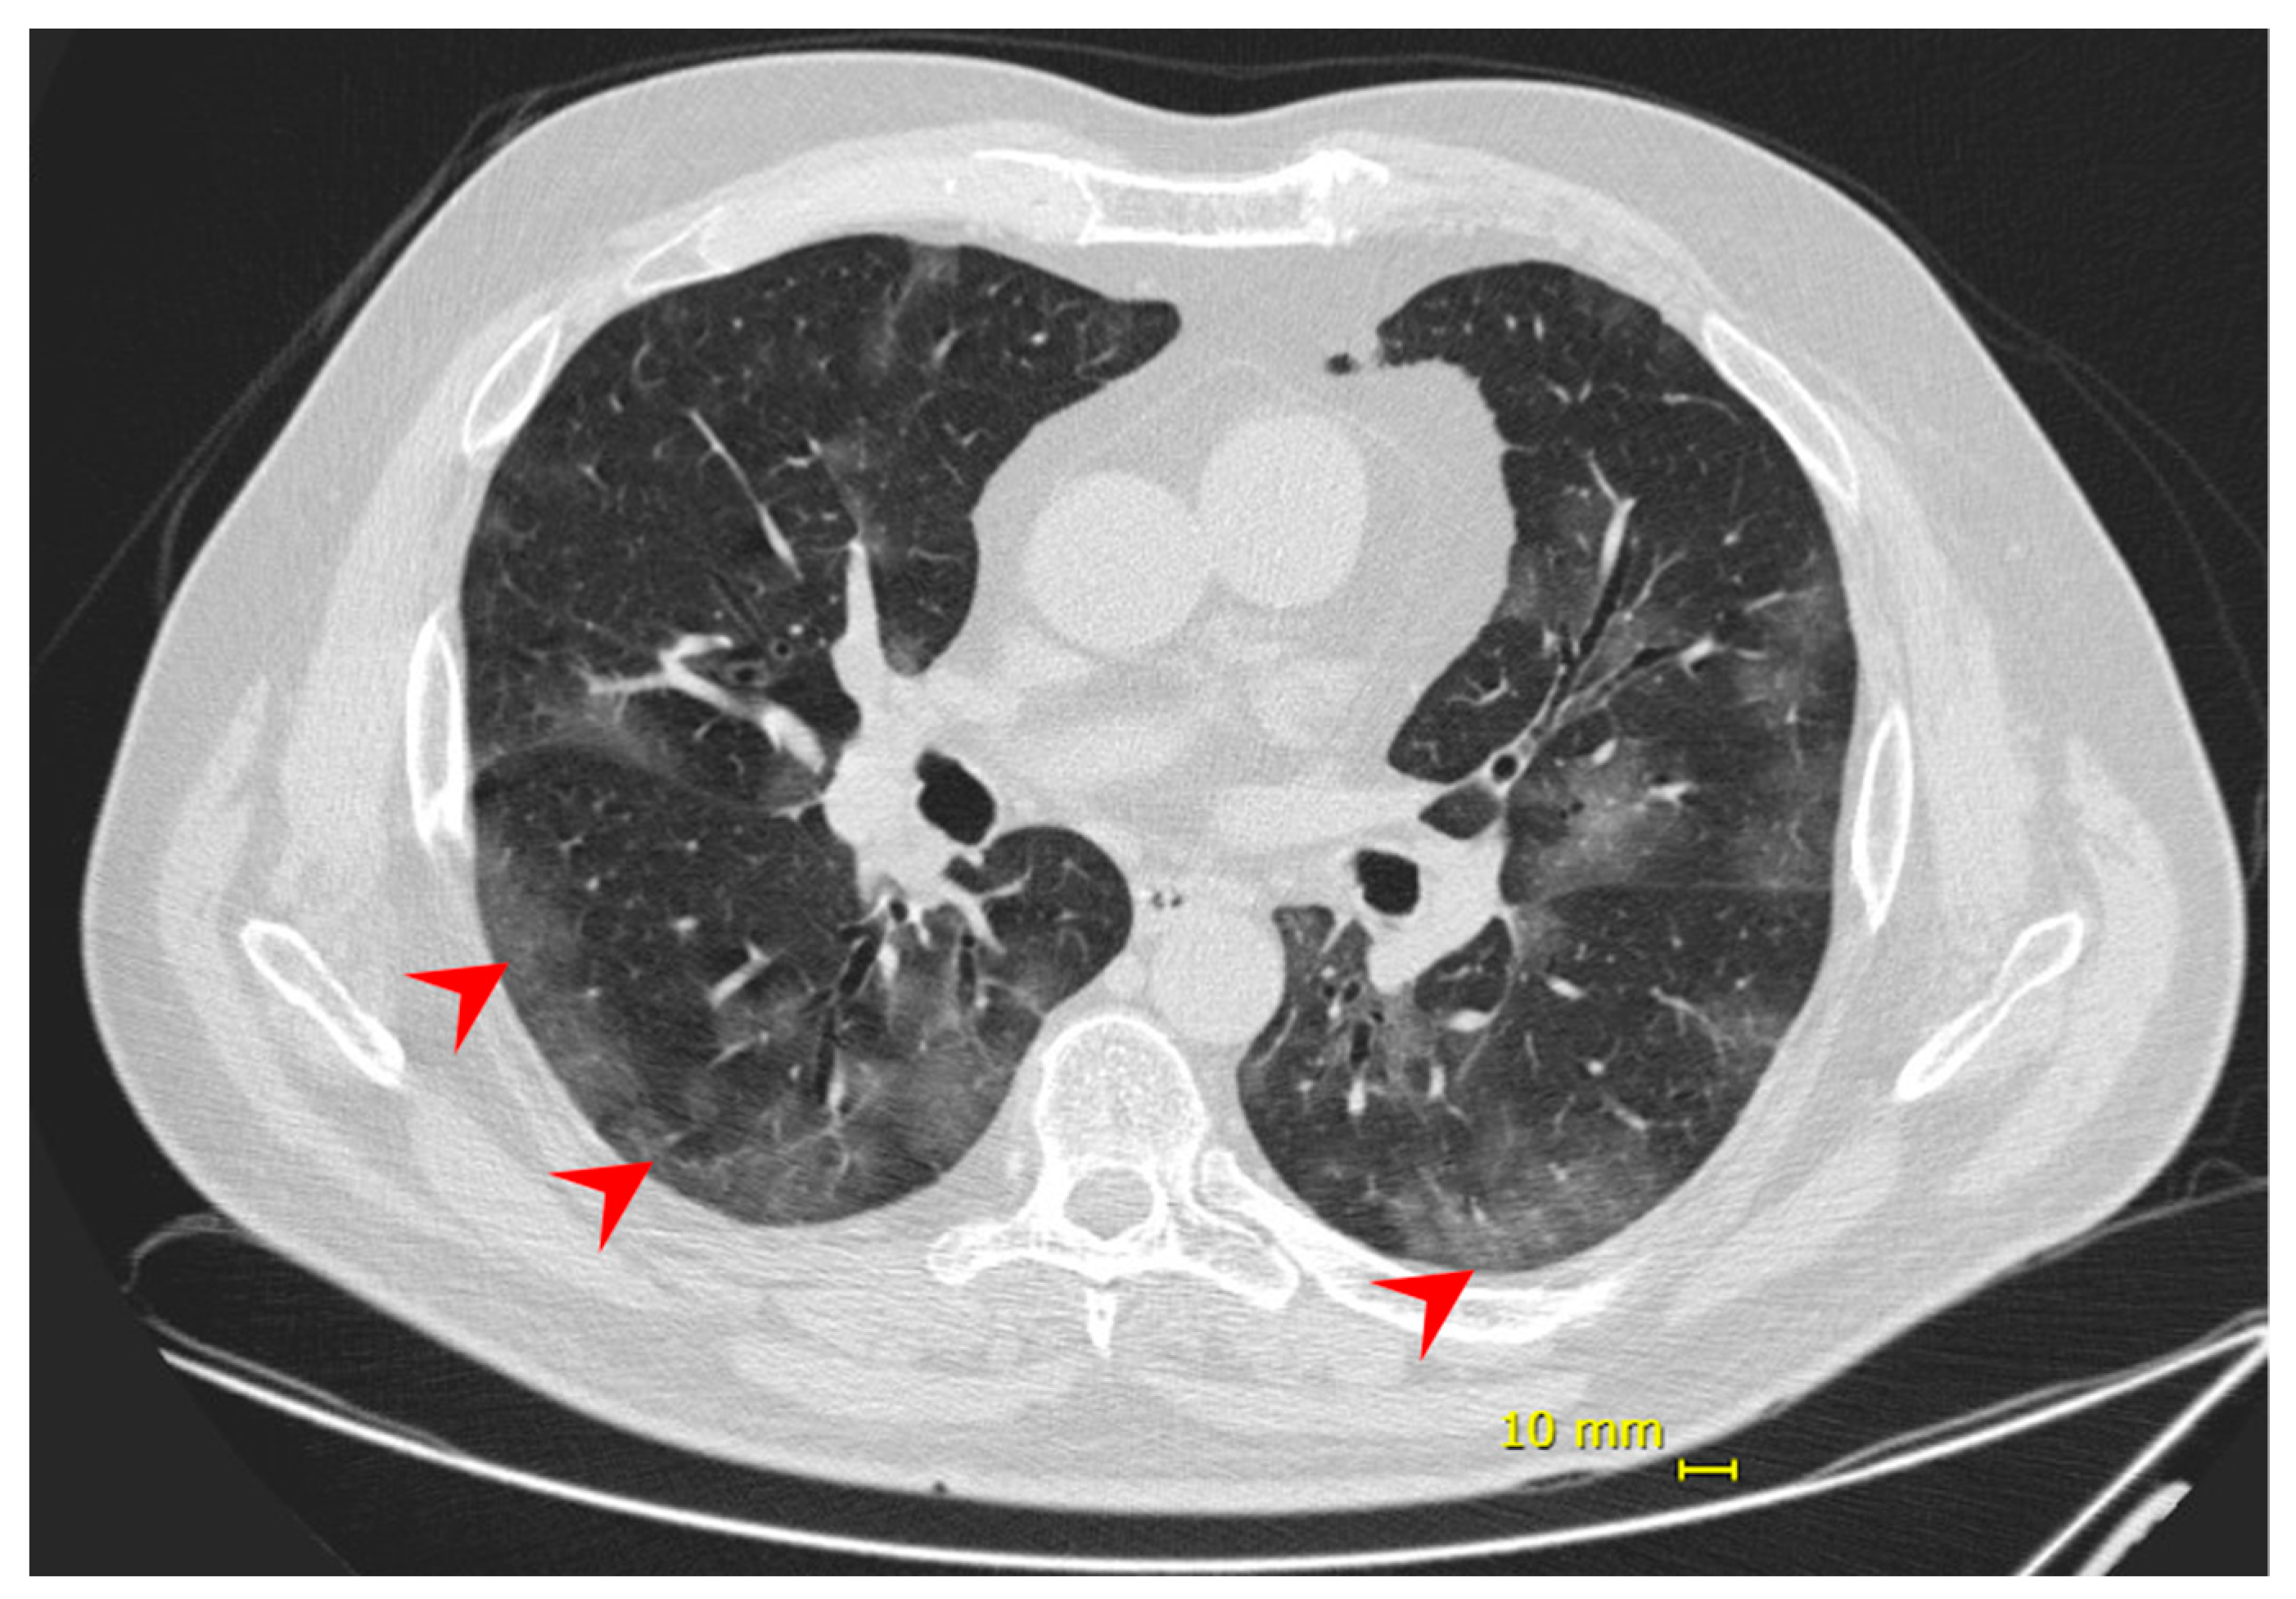

| Chest CT | Bilateral multifocal ground-glass opacities (25–50%) predominantly peripheral and subsegmental atelectasis | Bilateral multifocal ground-glass opacities (<25%) predominantly peripheral, and subsegmental atelectasis | ||||||